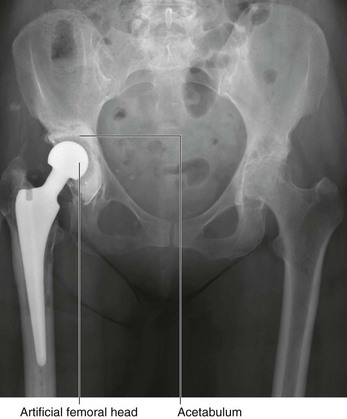

In the clinic Avascular necrosis

Avascular necrosis is cellular death of bone resulting from a temporary or permanent loss of blood supply to that bone. Avascular necrosis may occur in a variety of medical conditions, some of which have an etiology that is less than clear. A typical site for avascular necrosis is a fracture across the femoral neck in an elderly patient. In these patients there is loss of continuity of the cortical medullary blood flow with loss of blood flow deep to the retinacular fibers. This essentially renders the femoral head bloodless; it subsequently undergoes sclerosis and collapse. In these patients it is necessary to replace the femoral head with a prosthesis (Fig. 1.16).

image

Fig. 1.16 Image of the hip joints demonstrating loss of height of the right femoral head with juxta-articular bony sclerosis and subchondral cyst formation secondary to avascular necrosis. There is also significant wasting of the muscles supporting the hip, which is secondary to disuse and pain.

In the clinic Joint replacement

Joint replacement is undertaken for a variety of reasons. These predominantly include degenerative joint disease and joint destruction. Joints that have severely degenerated or lack their normal function are painful, which can be life limiting, and in otherwise fit and healthy individuals can restrict activities of daily living. In some patients the pain may be so severe that it prevents them from leaving the house and undertaking even the smallest of activities without discomfort.

Large joints are commonly affected, including the hip, knee, and shoulder. However, with ongoing developments in joint replacement materials and surgical techniques, even small joints of the fingers can be replaced.

Typically, both sides of the joint are replaced; in the hip joint the acetabulum will be reamed, and a plastic or metal cup will be introduced. The femoral component will be fitted precisely to the femur and cemented in place (Fig. 1.26).

Fig. 1.26 This is a radiograph, anterior-posterior view, of the pelvis after a right total hip replacement. There are additional significant degenerative changes in the left hip joint, which will also need to be replaced.

Most patients derive significant benefit from joint replacement and continue to lead an active life afterward.